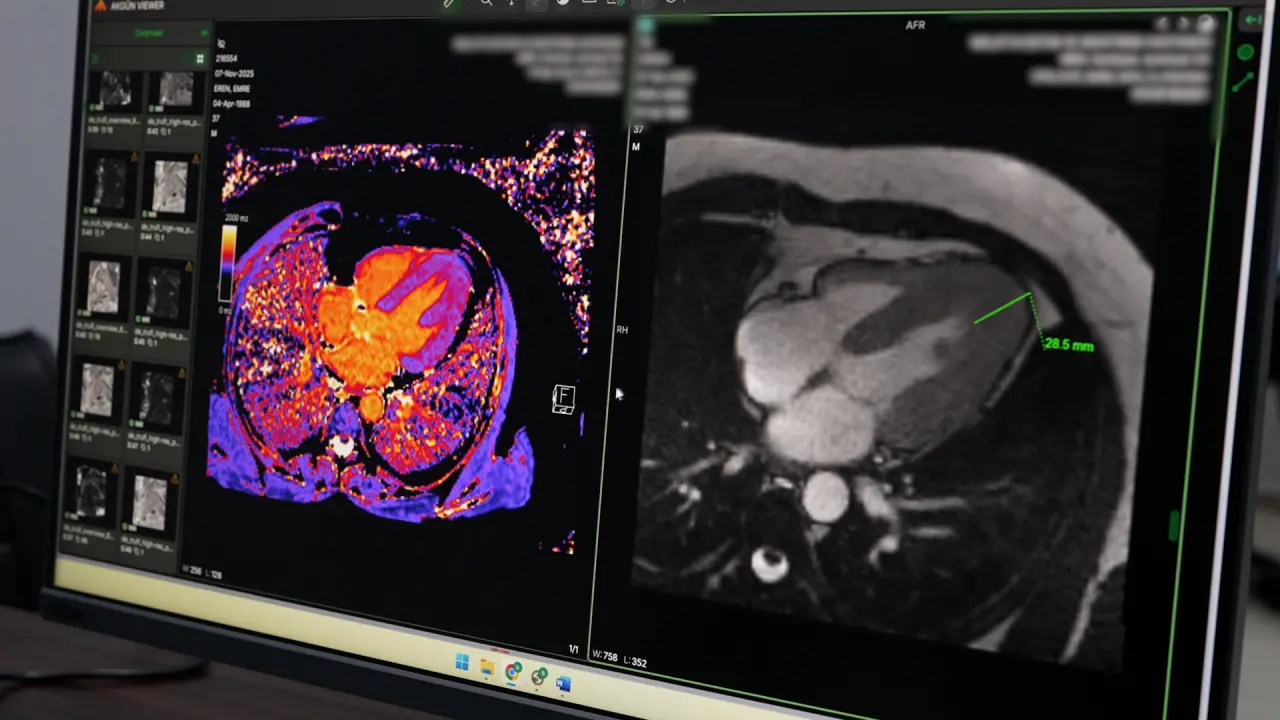

- Kardiyak MR: Kalp kası, kapak hastalıkları ve damarsal anomalilerin değerlendirilmesinde dünyada ön sıralarda yer alan bu teknolojiyle en ayrıntılı incelemeler yapılıyor.

Hastanenin teknik kapasitesinin tanı başarısına etkisine örnek veren Petik, kalp yetmezliği şikâyetiyle başvuran bir hastada yapılan incelemeler sonucunda nadir görülen Yamaguchi Sendromu tanısı konulduğunu açıkladı. Erken teşhis sayesinde hastanın tedavi süreci doğru planlanarak hayati risklerin önüne geçildi. Girişimsel radyoloji alanında da vasküler ve non-vasküler işlemlerin ameliyathane ortamında uygulanmaya başlandığı, altyapının her geçen gün daha da güçlendiği belirtildi.